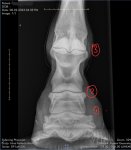

Random thought & I’m sure you’ve considered it but just in case… this is labelled as a DP view of the LH although annoyingly I can’t see a left / right positioning marker.

If the image hasn’t been flipped by the vet in their imaging software (& sometimes they will for certain reasons) that should mean that the beam would hit the front of the foot first & then pass through the back. I think that might make what is on the left hand side of the image be the right hand side of the foot & vice versa? Please note this is based on how I’d expect a dog limb to look if I xrayed in that view & so may be wrong but just a thought if you’re thinking the flare seems to appear on the wrong side on X-ray as I’d expect the shape of the outer wall visually to correspond pretty well with how the outline of the foot appears on X-ray

I agree it looks confusing but think the flare is where it needs to be.

My reasoning is that the leg, on my screen, bends over to the right as it goes up. So, the weight will be more over to the right of the foot than centre. The flare is also on the right, moving the centre of the foot to under where the weight will be. Hence, re-balancing naturally the surface area to under the centre of gravity.